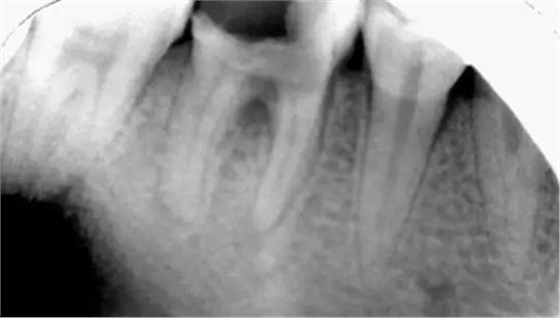

初診時X光片:根分歧炎癥懷疑有底穿,和患者交待病情和費用后開始治療。